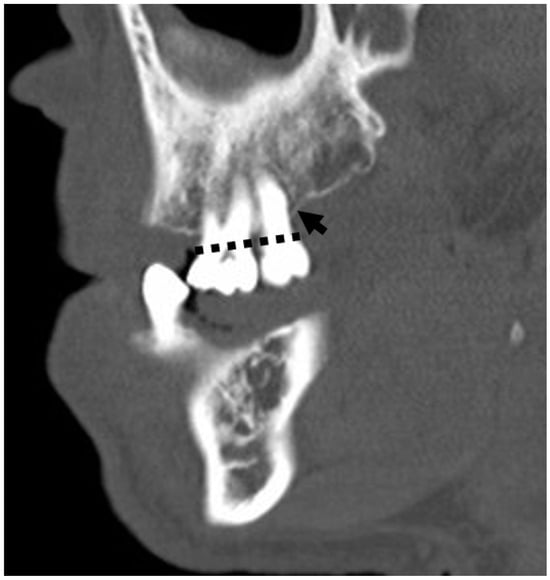

3.5.4. Periodontal Disease Radiologic Correlations

3.5. Anatomical and Imaging Correlations to Odontogenic Infectious Disease